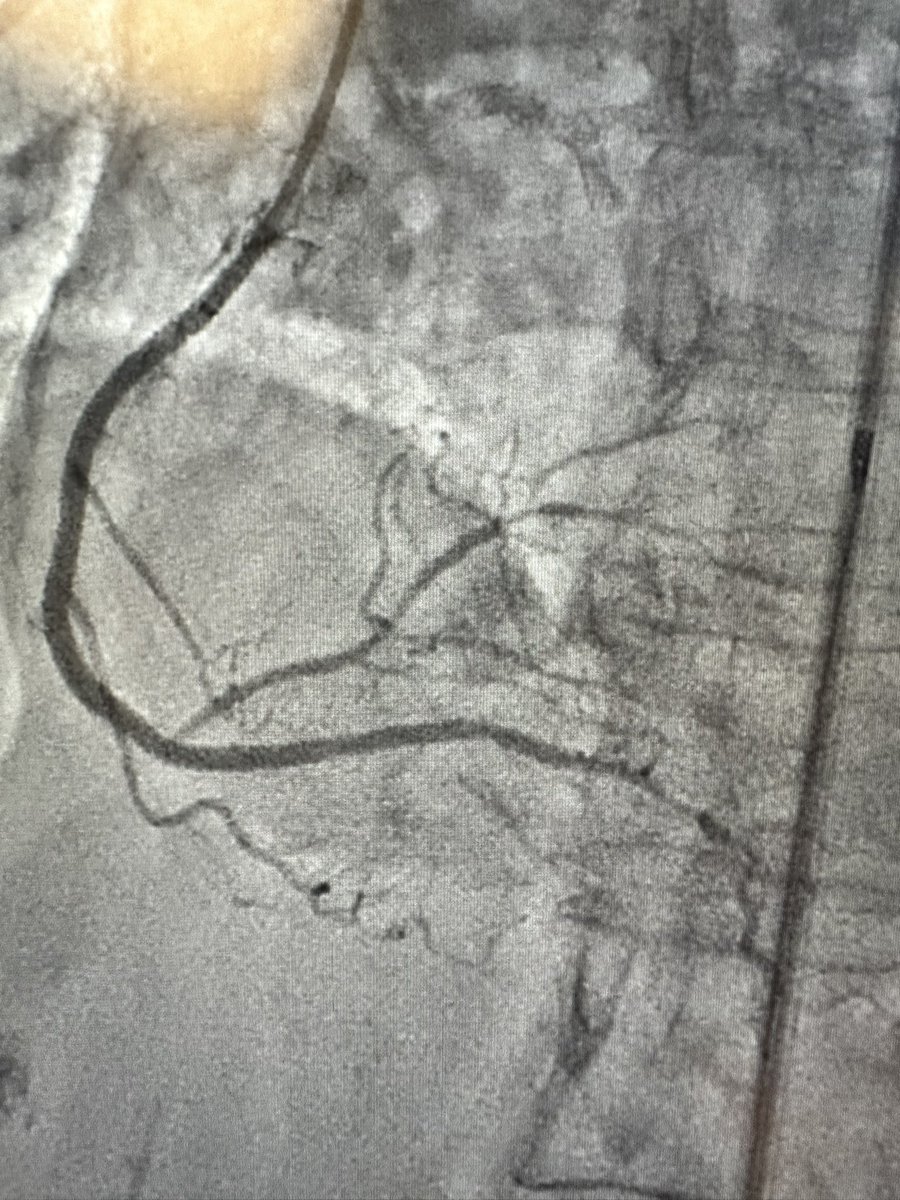

Interesting situation in patient with challenging access options with flush occluded ostial RCA. Able to wire retro and externalize in single EBU guide in the descending aorta before switching antegrade and stent.@jgpugedamd